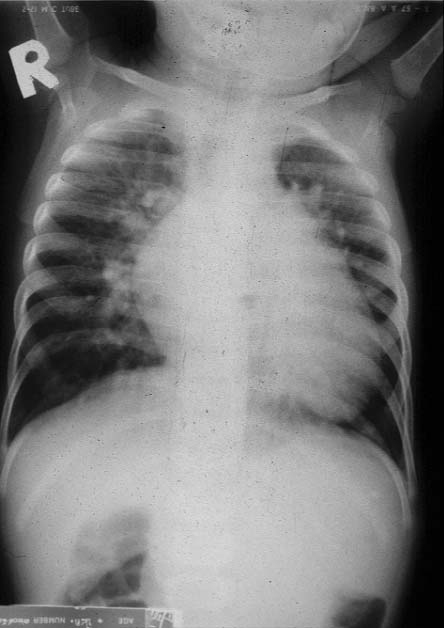

Chest x-ray : Cardiomegaly (egg lying pattern)  with increase pulmonary vascularity

ลักษณะการเปลี่ยนแปลงการไหลเวียนของโลหิตในผู้ป่วยรายนี้เป็นแบบ right to left shunt with abnormal of systemic and pulmonary veins to aorta or pulmonary artery เนื่องจากผู้ป่วยมีอาการเขียวร่วมกับมีลักษณะ

increase pulmonary vascularity ในภาพรังสีปอด ลักษณะที่พบเกิดจากการที่มี bidirectional shunt  จึงทำให้มีปริมาณโลหิตที่ไหลไปปอดเพิ่มขึ้น ดังนั้นการวินิจฉัยแยกโรคได้แก่ TGA, TGA with VSD, Truncus type I,II,III, DORV